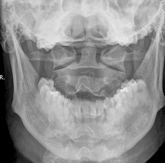

Columna Cervical Transoral

Igual posición que en proyección AP. La boca del paciente abierta ampliamente, y el haz de rayos dirigido al centro de la boca. El paciente debe estar en fonación (“aaaa”) durante la exposición, manera de desproyectar la lengua.